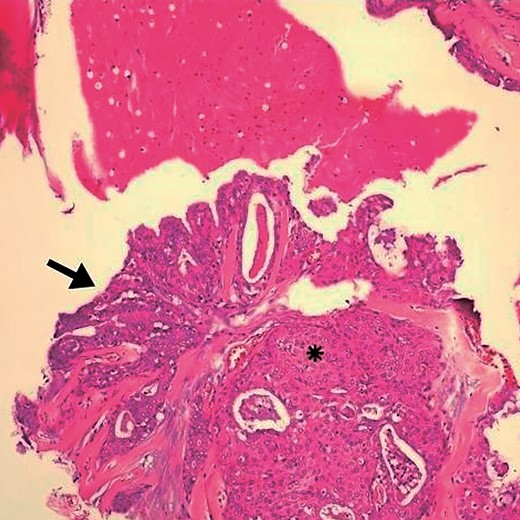

Detail of Fig. 1. Arrow indicates goblet cells and changes indicative of glandular epithelium. (*) area with squamous differentiation. HE, ×10.